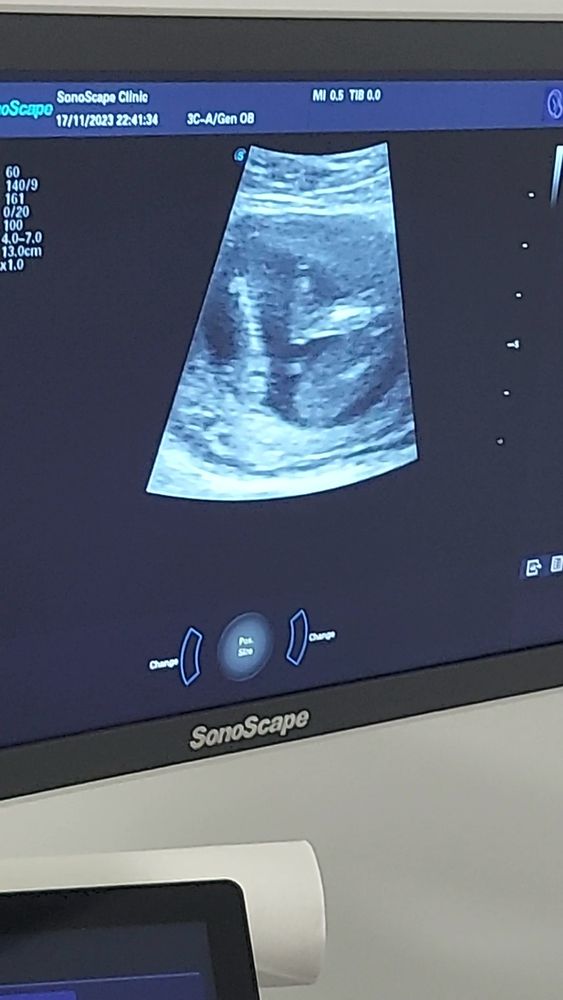

Сегодня узнаем кто в домике живет) (много фото узи) а вы как думаете?)

Плохое качество фото, видно что все они сняты между ног, но не чётко, вообще яичек нет вроде бы, значит девочка.

УЗИ 12 недель Точно девочка?)